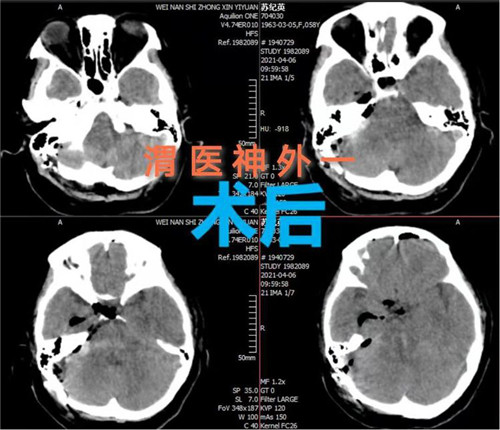

手术计划制定后,即刻安排手术,手术麻醉科确定了由麻醉医师钟永慧、配合护师党海婷和马丹组成的麻醉护理团队。手术历时近4个小时,手术过程患者生命体征平稳,术中总出血量约50毫升,术后患者恢复自主呼吸。术后次日患者生命体征平稳,意识恢复,右侧肢体活动正常,左侧肢体活动正在恢复中。

脑干出血病死率和致残率较高。因为脑干的生命中枢功能及其位置深、体积小的特点,脑干手术一直被视为手术禁区,术中稍有不慎将造成严重神经障碍,甚至死亡。此次手术的成功实施,是市中心医院神经外科一病区医生们挑战手术禁区,勇攀技术高峰,守护患者生命中枢的充分体现。